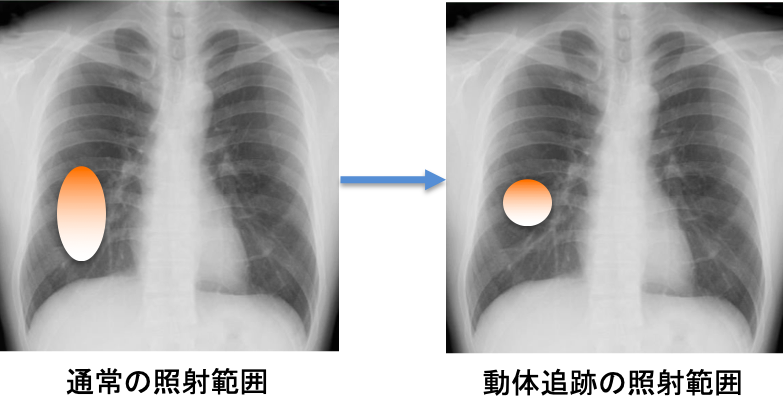

加えて、当院には県内で唯一(2021年4月時点)となる動体追跡システムが導入されています。肺や肝臓などの臓器は呼吸に伴って1cmから2cm程度の上下動を繰り返しています。そのため、ピンポイントの放射線治療を行う際の精度が落ちる可能性があったり、放射線を当てる範囲を大きくしたりする必要があります。治療を行う際、このシステムを使用することで、腫瘍近傍の肺や肝臓の動きをリアルタイムに観測することができ、腫瘍が特定の位置に来た時のみ、放射線を当てることが可能となります。そのため、照射範囲を縮小し、よりピンポイントに、より安全に治療を行うことが可能です。動体追跡を用いた治療を行う際には事前に金製のマーカーを腫瘍近傍に挿入する必要がありますが、そういった処置が可能な場合、当院では積極的に動体追跡を併用した定位放射線治療を行なっています。安全性の問題から動体追跡を併用した方が望ましい場合、新潟市や長岡市などの他の医療圏からの紹介で治療を行うこともあります。現在、当院では早期肺癌や肝臓癌に限定して動体追跡放射線治療を行なっております。対象となる方でご興味をお持ちの方は一度ご相談ください。